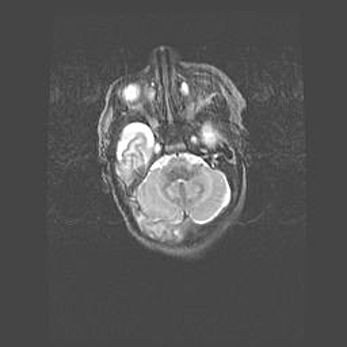

Церебральная ишемия II.

Возраст: 5 дней

Вес: 3400 г

Пол: женский

Окружность головы: 35 см

Срок гестации: 39 недель

Церебральная ишемия – это заболевание, характеризующееся недостаточностью (гипоксией) либо полным прекращением (аноксией) снабжения мозга кислородом по причине закупорки одного или нескольких сосудов. Это приводит к  что метаболическим расстройствам различной степени тяжести в тканях головного мозга, развитию коагуляционных некрозов и гибели нейронов.